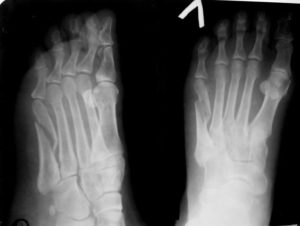

Снимок плюсневой кости делается в нескольких проекциях: прямой, боковой и полу боковой. Некоторые виды перелома могут потребовать повторного снимка, и особой укладки стопы пострадавшего человека.

Фото с рентген снимком стопы, на которой четко изображен перелом пятой плюсневой кости

Вызвать затруднение во время постановки диагноза может рентгенограмма перелома основания кости без смещения обломков, особенно это касается 3-4.

Это можно объяснить специфическим наложением теней, при стандартном методе расположения стопы, поэтому подобные случаи требуют особого ракурса, во время которого стопа укладывается под углом 35-45 градусов (положение пронации).